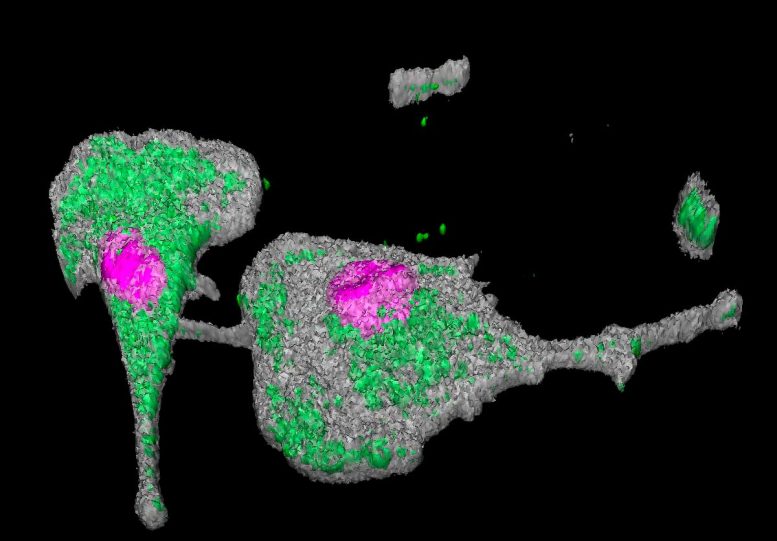

L’étude a montré que le virus SARS-CoV-2 se transmet d’un macrophage à un autre via des projections cellulaires en forme de pont, lui permettant de se propager. Le noyau cellulaire est surligné en rose et la protéine virale NSP3 est surlignée en vert. Crédit : © Marie Lazzerini, Nicolas Huot, Institut Pasteur

« Nous avons été très surpris de retrouver des virus dans certaines cellules immunitaires – les macrophages alvéolaires – après une si longue période et alors que les tests PCR réguliers étaient négatifs », souligne Nicolas Huot, premier auteur de l’étude et chercheur à l’Institut Pasteur VIH, Inflammation et Unité de persistance. « De plus, nous avons cultivé ces virus et avons pu observer, grâce aux outils que nous avons développés pour étudier le VIH, qu’ils étaient encore capables de se répliquer. »

Pour comprendre le rôle de l’immunité innée dans le contrôle de ces réservoirs viraux, les scientifiques se sont ensuite tournés vers les cellules NK (natural killer). «La réponse cellulaire de l’immunité innée, qui constitue la première ligne de défense de l’organisme, a jusqu’à présent été peu étudiée dans les infections par le SRAS-CoV-2», explique Michaela Müller-Trutwin. « Pourtant, on sait depuis longtemps que les cellules NK jouent un rôle important dans le contrôle des infections virales. » L’étude montre que chez certains animaux, les macrophages infectés par le SRAS-CoV-2 deviennent résistants à la destruction par les cellules NK, tandis que chez d’autres, les cellules NK sont capables de s’adapter à l’infection (appelées cellules NK adaptatives) et de détruire les cellules résistantes. cas des macrophages.

L’étude a donc mis en lumière un mécanisme qui pourrait expliquer la présence de « réservoirs viraux » : alors que les individus avec peu ou pas de virus à long terme avaient une production adaptative de cellules NK, les individus avec des niveaux plus élevés de virus n’avaient pas seulement une absence de cellules NK adaptatives. cellules, mais également une réduction de l’activité des cellules NK. L’immunité innée semble donc jouer un rôle dans le contrôle des virus SARS-CoV-2 persistants.